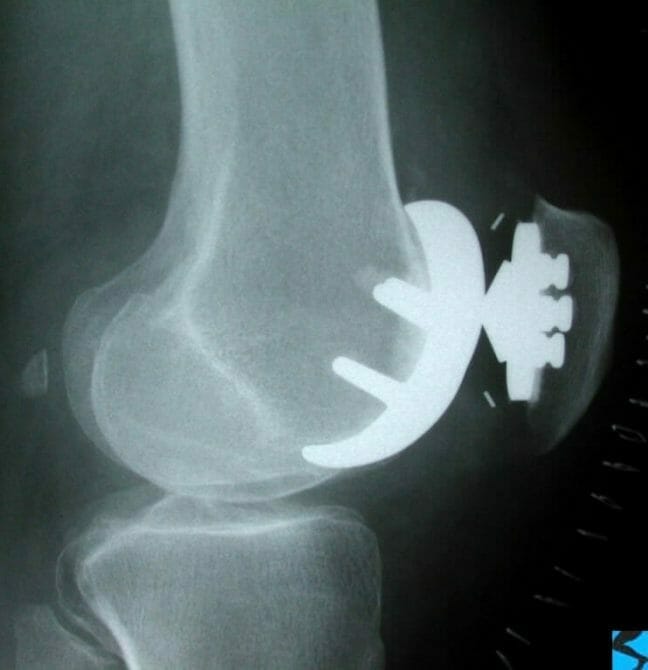

Skyline view of patellofemoral joint showing patellofemoral arthritis with loss of lateral patella joint space and lateral tilt of the patella.